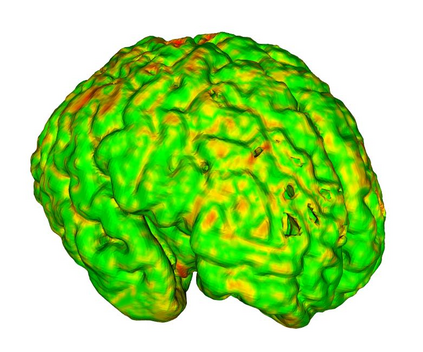

Fetal cortical plate segmentation is essential in quantitative analysis of fetal brain maturation and cortical folding. Manual segmentation of the cortical plate, or manual refinement of automatic segmentations is tedious and time-consuming. Automatic segmentation of the cortical plate, on the other hand, is challenged by the relatively low resolution of the reconstructed fetal brain MRI scans compared to the thin structure of the cortical plate, partial voluming, and the wide range of variations in the morphology of the cortical plate as the brain matures during gestation. To reduce the burden of manual refinement of segmentations, we have developed a new and powerful deep learning segmentation method. Our method exploits new deep attentive modules with mixed kernel convolutions within a fully convolutional neural network architecture that utilizes deep supervision and residual connections. We evaluated our method quantitatively based on several performance measures and expert evaluations. Results show that our method outperforms several state-of-the-art deep models for segmentation, as well as a state-of-the-art multi-atlas segmentation technique. We achieved average Dice similarity coefficient of 0.87, average Hausdorff distance of 0.96 mm, and average symmetric surface difference of 0.28 mm on reconstructed fetal brain MRI scans of fetuses scanned in the gestational age range of 16 to 39 weeks. With a computation time of less than 1 minute per fetal brain, our method can facilitate and accelerate large-scale studies on normal and altered fetal brain cortical maturation and folding.